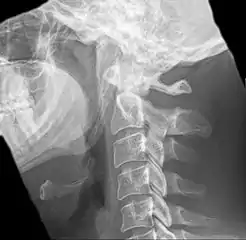

Radiograph, lateral view showing elongated stylohyoid process and stylohyoid ligament ossification

Imaging is important and is diagnostic. Visualizing the styloid process on a CT scan with 3D reconstruction is the suggested imaging technique.[11] The enlarged styloid may be visible on an orthopantogram or a lateral soft tissue X ray of the neck.